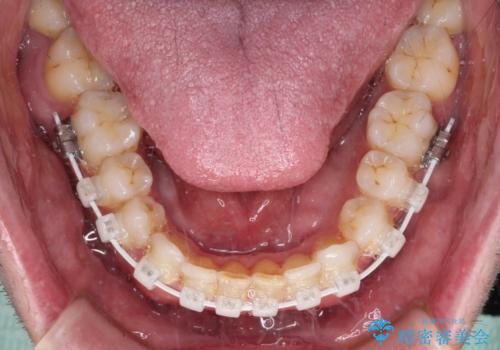

- 審美装置

前歯の非接触改善は、インビザラインの得意とするところですが、マウスピース矯正は絶対に継続できないとのことで、ワイヤー装置にて矯正治療を行うこととしました。